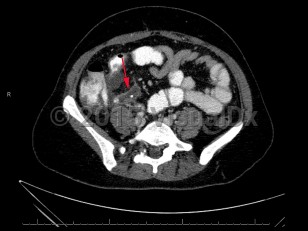

Imaging Studies image of Acute appendicitis - imageId=7873162. Click to open in gallery.  caption: 'Contrast enhanced axial image from CT scan demonstrating distended appendix with appendicolith.'

Contrast enhanced axial image from CT scan demonstrating distended appendix with appendicolith.